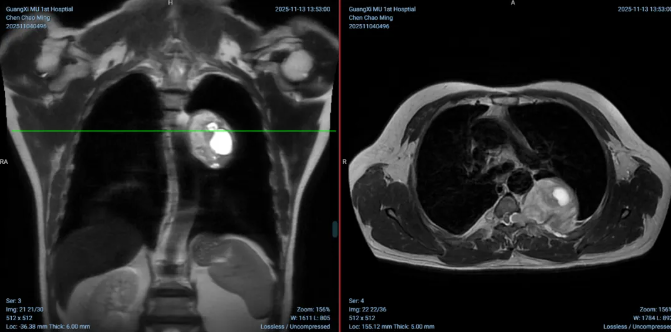

近日,广西医科大学第一附属医院脊柱骨病外科团队与胸外科纵隔专业组团队成功为一名罹患巨大胸主动脉旁神经鞘瘤的患者实施...